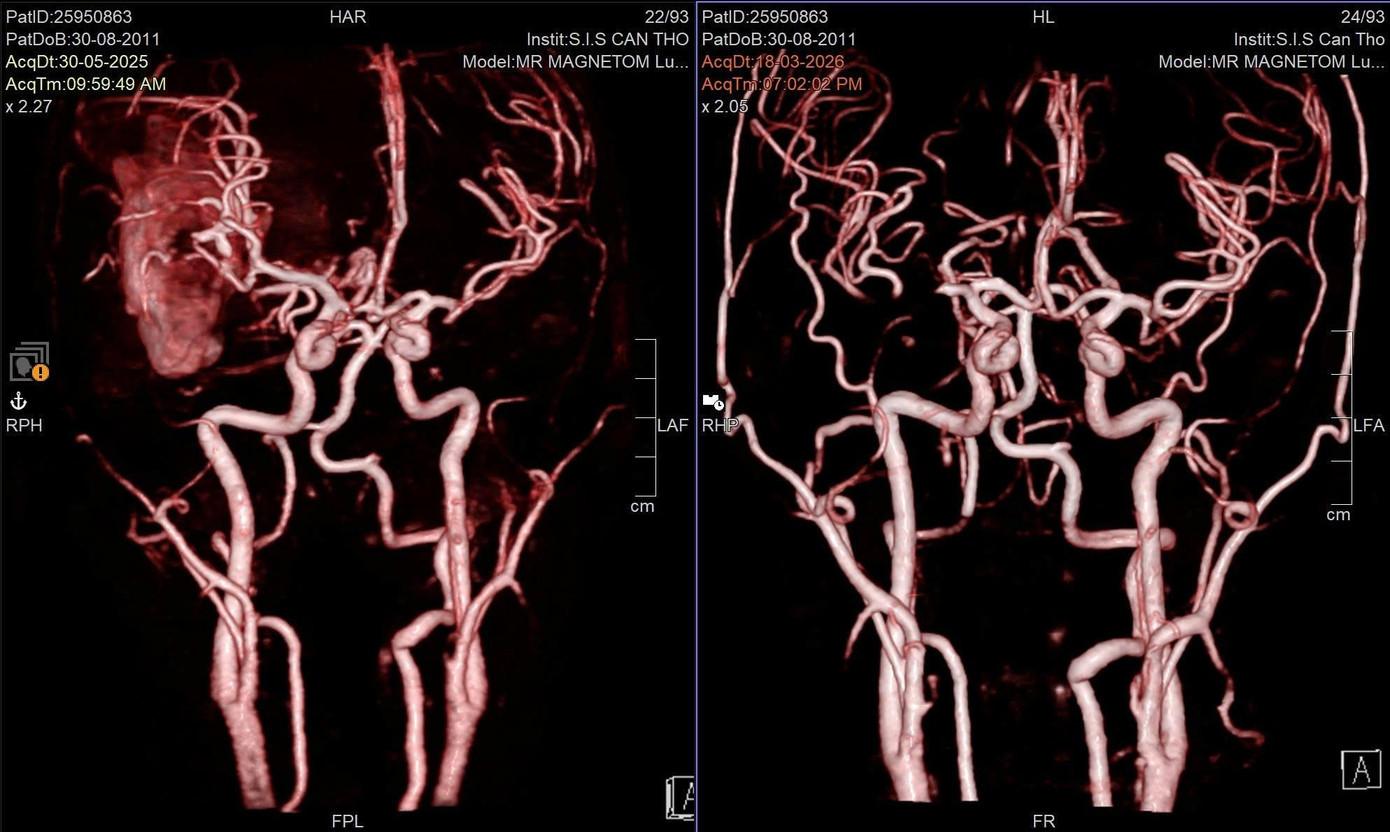

Hệ thống mạch máu não của bệnh nhân trước và sau khi được can thiệp xử lý túi phình bị vỡ

Đến ngày thứ 5, cơn đau đầu tái phát với mức độ nghiêm trọng hơn. Bệnh nhân xuất hiện yếu liệt nửa người bên trái, sau đó rơi vào hôn mê. Gia đình nhanh chóng đưa em đi cấp cứu trong tình trạng nguy kịch. Qua thăm khám, chẩn đoán chuyên sâu, các bác sĩ xác định T. bị xuất huyết não do vỡ dị dạng mạch máu não (AVM). Đây là một bệnh lý bẩm sinh nguy hiểm, có thể diễn tiến âm thầm trong thời gian dài và bộc phát đột ngột.

Theo BS-CKI Nguyễn Quang Hưng, Trưởng Đơn vị Phẫu thuật Thần kinh của bệnh viện, bệnh nhân có dị dạng mạch máu não phức tạp kèm khối máu tụ lớn, nguy cơ tử vong cao nếu không được can thiệp kịp thời. Ê kíp đã triển khai chiến lược điều trị phối hợp nhằm kiểm soát chảy máu và loại bỏ tổn thương.

Ngay khi nhập viện, bệnh nhân được cấp cứu, đánh giá nhanh và tiến hành can thiệp nội mạch để giảm lưu lượng dòng chảy, hạn chế nguy cơ chảy máu tiếp diễn. Sau đó, ê kíp phẫu thuật thần kinh thực hiện bóc tách và loại bỏ hoàn toàn khối dị dạng. Ca can thiệp diễn ra khẩn trương giúp bảo tồn tối đa chức năng não. Sau phẫu thuật, bệnh nhân tỉnh lại chỉ sau một đêm, diễn tiến hồi phục tích cực.